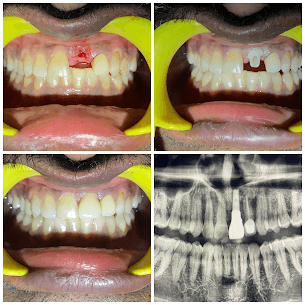

- TREATMENTS:

Two-Stage Implant

- INFO:

Single tooth replacement with two-stage implant for 30-year-old female